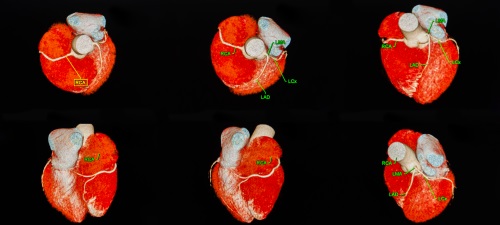

3b. 冠狀動脈造影(Coronary CT angiography, CTA)

冠狀動脈造影的原理,是利用高速多層螺旋電腦掃描器(Multiple detector computed tomography, MDCT)來掃描出多張心臟及心血管的橫切面圖片,然後拼砌出一個3D心臟影像,醫生就能準確診斷出早期冠狀動脈梗塞及心血管中極微量的鈣化現象,來評估患者出現冠心病的風險。